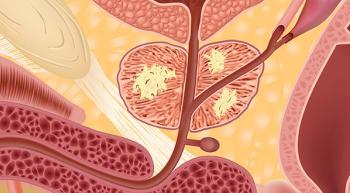

The FDA has granted a priority review to a new drug application (NDA) for apalutamide (ARN-509) for the treatment of patients with nonmetastatic castration-resistant prostate cancer (CRPC). Apalutamide is an oral androgen receptor inhibitor.